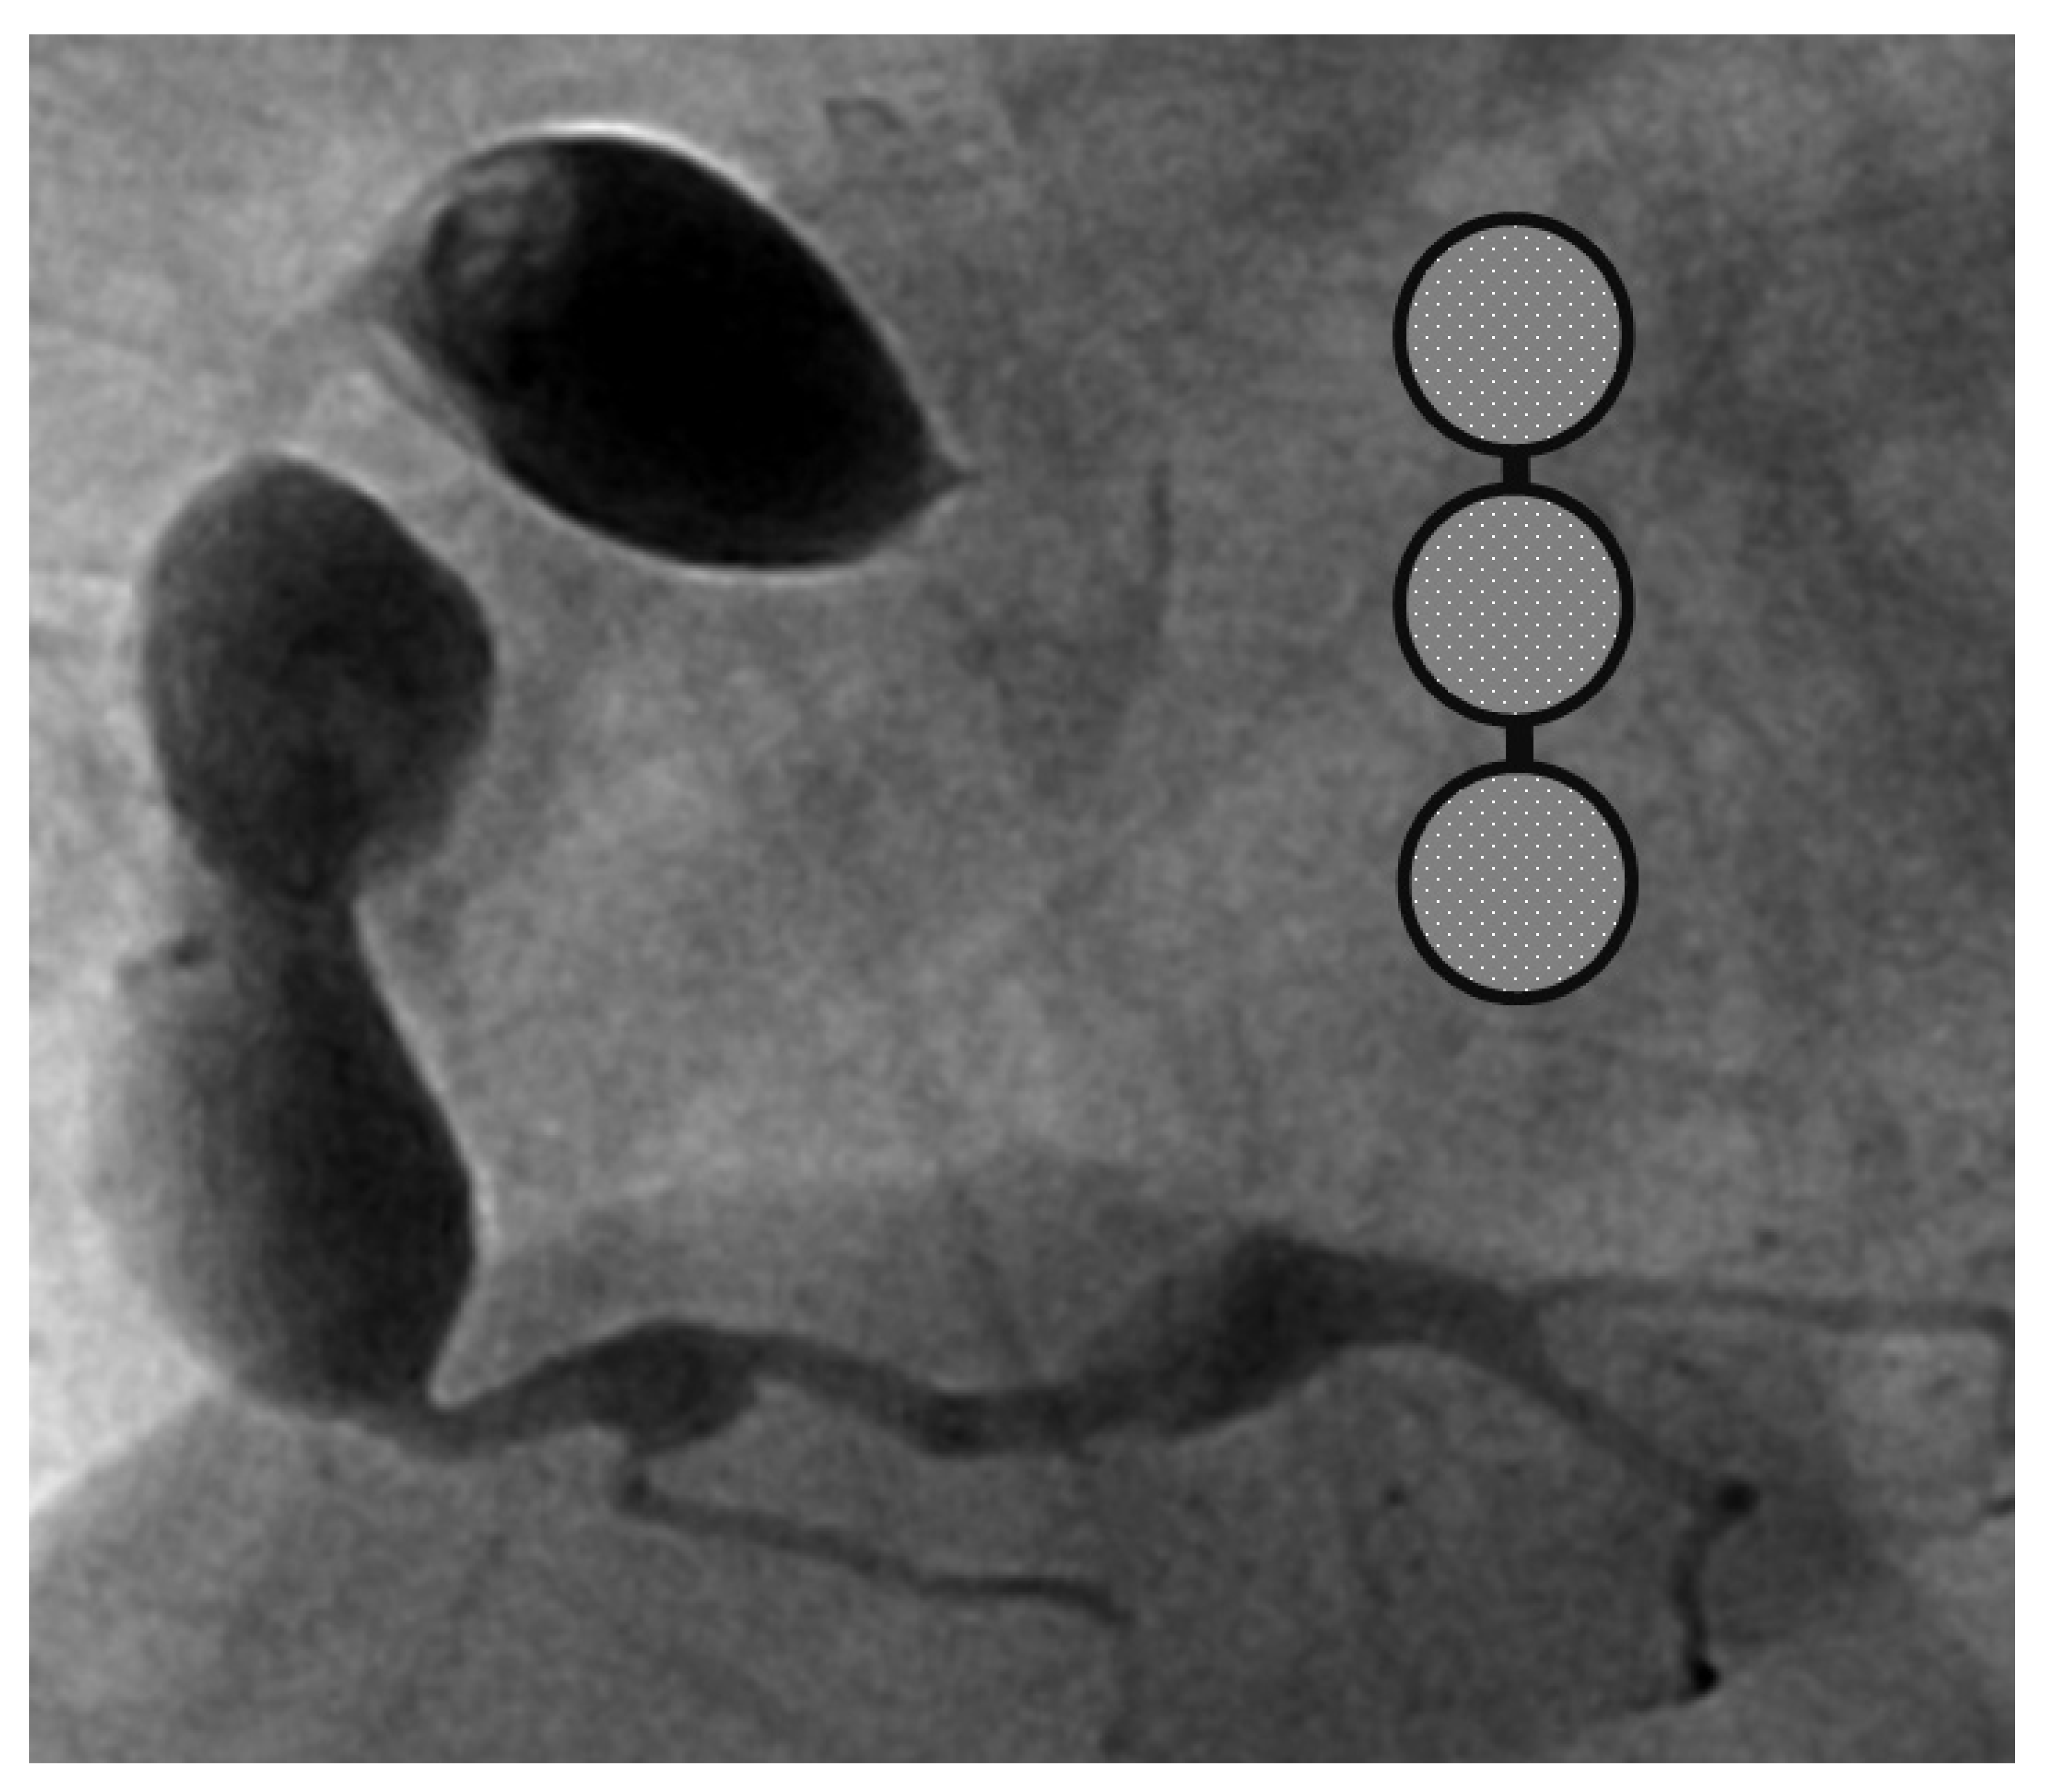

A 4-month-old infant girlwho presented with intermittent fever without explanation for 14 days was admitted.Laboratorydata revealed leukocytosis (19.5 × 109/L), high sensitivityC-reactive protein (CRP, 1139.04 nmol/L), and thrombocytosis (590 × 109/L). Negative culture reports were found in blood and urine. The empirical antibiotics administration did not achieve clinical improvement. The subcostal view of echocardiography andtransthoracic echocardiography (TTE) revealed three giant fusiform aneurysms of the proximal right coronary artery, along with other smaller aneurysms in the left coronary system. (Figure 1) Acute mitral insufficiency with moderate pericardial effusion was also present. The three beaded aneurysms were subsequently confirmed on a selective right coronary angiogram. (Figure 2) The fever resolved after receivinga high-dose intravenous immunoglobulin (IVIG) infusion. Aspirin with anticoagulant drugs (subcutaneous injection of low molecular weight heparin) administration was initiated and serial echocardiography as well as invasive coronary angiography follow-up were regularly performed sincethe giant aneurysm’s detection. (Figure 3) This report revealeda “beaded aneurysm” as a special medical image for KD.Itsfundamental nature of non-contiguous aneurysms could be a key to identifying antecedent KD vasculopathy compared toother coronary artery aneurysms. Written informed consent was obtained from the participant for the publication of this case report.

A pediatrician must check the echocardiography imaging of coronary arteries in infants with prolonged fever and evidence of elevated inflammation markers whenever the reasonable cause is absent because positive echocardiography findings were regarded as a set standard for acute KD accordingly. Coronary aneurysms can occur in up to 25% of KD children without a timely infusion of high-dose IVIG such as in this index case.As coronary aneurysms have become rare due to the widespread use of IVIG therapy for KD, beaded aneurysm is considered to be even rarer. There are no reports on the frequency of beaded aneurysms in KD, but it is presumed to be relatively rare.The final size of coronary aneurysms defines the future risk stratification generally speaking. In small or medium-sized aneurysms (<8mm or Z score <10), spontaneous regression of the aneurysms without significant cardiovascular sequela such as long-term luminal myofibroblastic proliferation is possible. In this case, the subcostal view of echocardiography and TTE revealed three giant fusiform aneurysms of the proximal right coronary artery, along with other smaller aneurysms in the left coronary system (Figure 1a–c). The three beaded aneurysms were confirmed by coronary angiogram is showed in Figure 2. In contrast with smaller aneurysms, giant aneurysms (>8 mm or Z score >10) seldom or never regress over time, which could be observed from the timeline of the index case(Figure 3).

Figure 2. Selective right coronary aneurysm was showed in this figure. Right coronary angiogram showed a beaded pattern of a saccular/fusiform aneurysm.